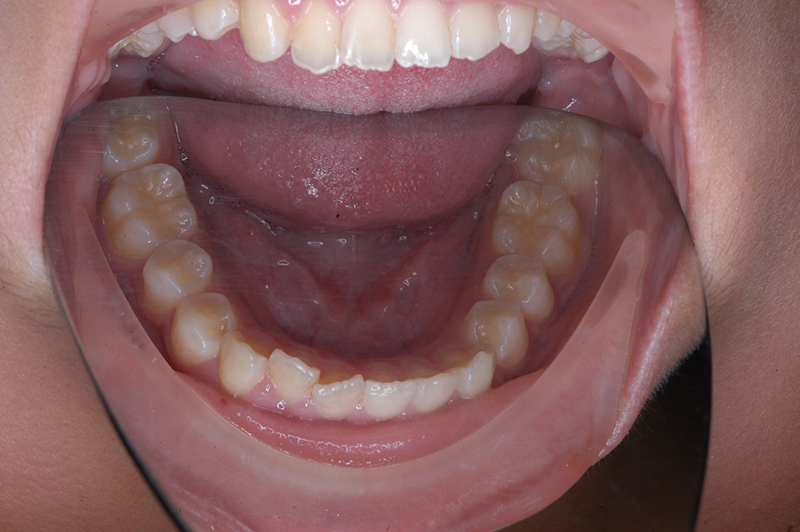

初診時

FP・IOP

主訴 出っ歯 診断名 アングルⅡ級1類

初診時年齢 10歳2ヵ月 性別 動的治療期間 23ヵ月

口腔内所見 大臼歯関係は右側がエンドオンのclassⅡ、左側がfull classⅡ。 上顎正中は下顎正中に対して僅かに右側偏位しており、上顎前歯は大きく唇側傾斜しover jetが11.0mmと上突咬合を呈していた。また下顎歯列の緩やかなスピーカーブのため過蓋咬合(over biteは5.0mm)となっていた。